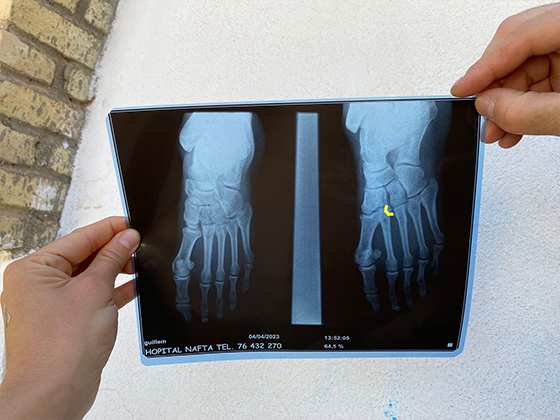

Pero... Guillem se sube en un banco de arena para darle caña a la moto, con tan mala suerte que sale despedido al lado contrario y da tremendo avionazo contra el asfalto. Yo lo veo en directo y me pongo amarillo y luego blanco. En seguida me acerco a él, que inmediatamente sabe que tiene dañado un pie. Le han caído encima los 220 kilos de la Teneré, más la inercia. Hacemos las primeras valoraciones y algunas curillas de poca monta y nos vamos de vuelta al pueblo, que por suerte está a sólo unos pocos kilómetros dando la vuelta por asfalto.

El personal es muy amable, pero algo confusionador. Y el seguro de viaje no ayuda mucho. Por fin conseguimos que le hagan una foto a los huesos y no se ve mucho daño, menos mal. Eso sí, el pie parece como cuando fermenta un tetrabrik.